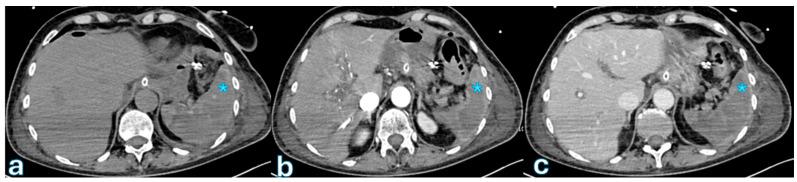

Radiological assessment following pancreaticoduodenectomy is critical for the prompt diagnosis and management of postoperative complications, significantly influencing patient outcomes. Pancreaticoduodenectomy, or the Whipple procedure, is the standard surgical intervention for pancreatic and periampullary malignancies, but it involves notable risks, especially from complications like fistulas, bleeding, or leakage. Cross-sectional imaging, particularly contrast-enhanced computed tomography, serves as the primary diagnostic tool due to its rapid acquisition, high resolution, and effective delineation of postoperative anatomy and complications. Magnetic resonance imaging (with cholangiopancreatography and hepatobiliary contrast agents) complements CT by providing superior contrast resolution for specific complications, notably in the biliary system and pancreatic duct. This narrative review discusses various imaging techniques and their applications, highlighting characteristic radiological features of common postoperative complications. It underscores the importance of a multidisciplinary approach, emphasizing close collaboration between radiologists and surgeons to optimize surgical decision-making and improve patient management post-pancreatic surgery.

胰十二指肠切除术后的影像学评估对于术后并发症的及时诊断和处理至关重要,对患者预后有显著影响。胰十二指肠切除术,即惠普尔手术,是治疗胰腺和壶腹周围恶性肿瘤的标准外科手术,但该手术存在显著风险,尤其是瘘、出血或渗漏等并发症。横断面成像,特别是增强计算机断层扫描,因其采集速度快、分辨率高且能有效描绘术后解剖结构和并发症,成为主要的诊断工具。磁共振成像(结合磁共振胰胆管造影和肝胆对比剂)通过为特定并发症提供更高的对比分辨率来补充CT,尤其是在胆道系统和胰管方面。本叙述性综述讨论了各种成像技术及其应用,突出了常见术后并发症的特征性影像学表现。强调了多学科方法的重要性,强调放射科医生和外科医生之间密切合作,以优化手术决策并改善胰腺手术后的患者管理。